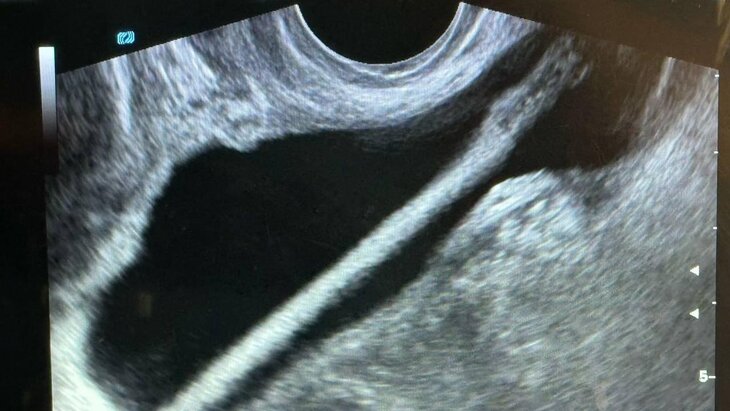

Заведующий отделением Петр Сысоев рассказал, что после проведения УЗИ пациентке была выполнена эндоскопическая операция, в ходе которой инородное тело удалили без осложнений. Сейчас женщина уже выписана домой.